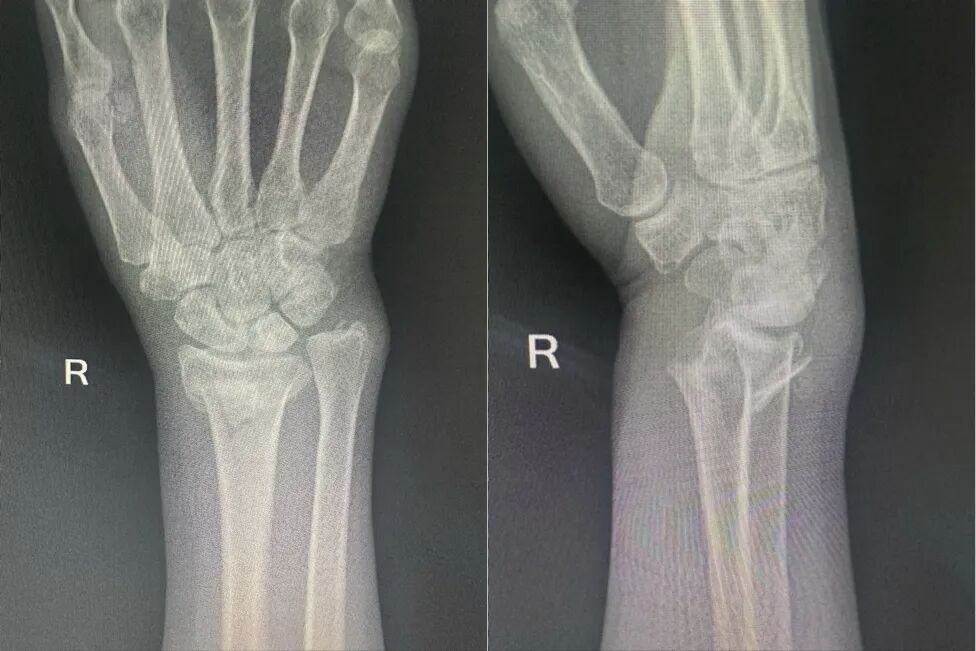

复位前

李阿姨不愿在异乡接受手术,担心影响归期,倍感焦虑。她的女儿突然想到了中医正骨,抱着试一试的心态,来到了西安市中医医院。赵军医师团队接诊后,充分评估患者情况,决定采用传统中医特色疗法——手法复位与小夹板固定。